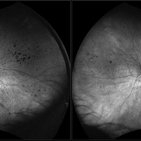

Retinitis Pigmentosa

Bilateral fundus autofluorescence images of retinitis pigmentosa.

Photographer: Olivia Rainey

Imaging device: Heidelberg Spectralis

Condition/keywords: 50 degrees, bilateral, fundus autofluorescence (FAF), hereditary retinal dystrophy, retinitis pigmentosa